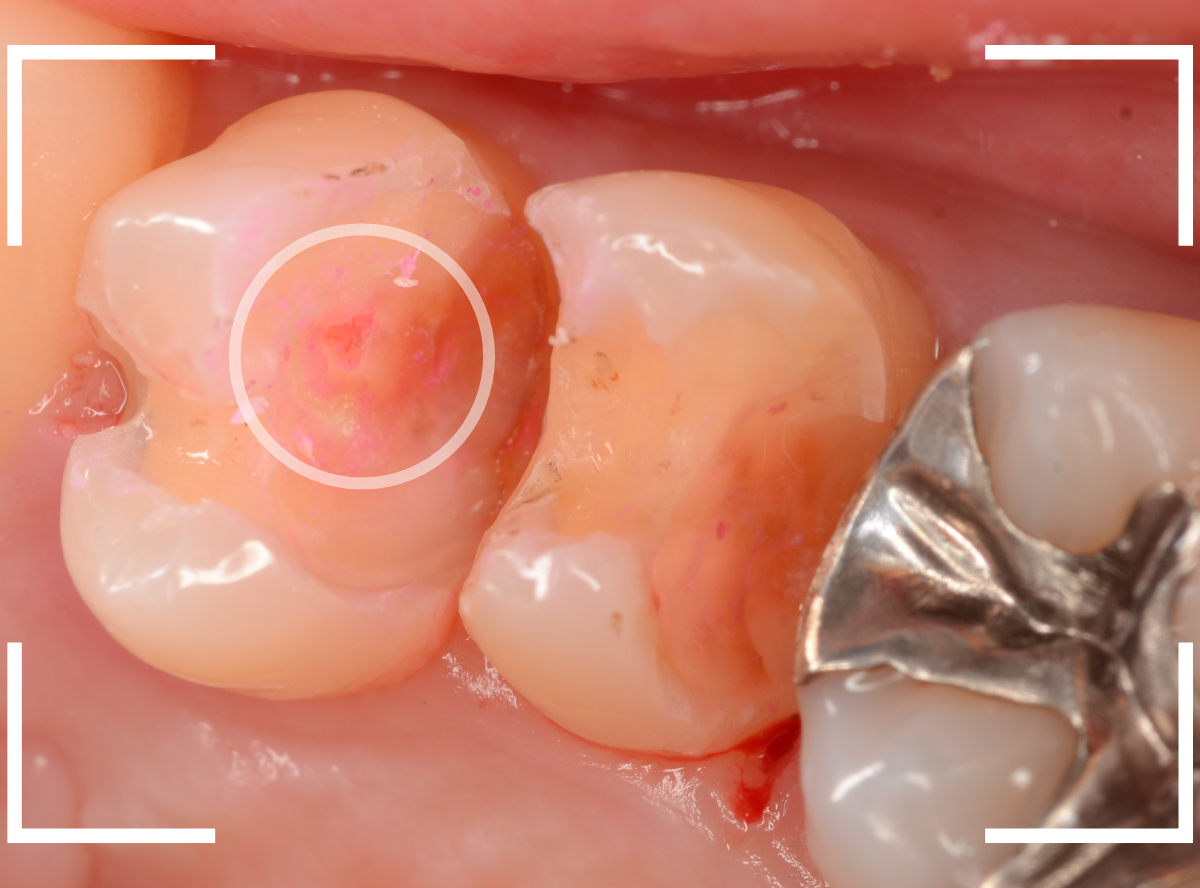

Case.22 痛みはないけど、歯のすきまから大きな虫歯

上の小臼歯の間が虫歯になっていた患者さんです。

症状はありませんし、見た目からも虫歯があるかはわかりませんでした。

レントゲン写真で確認します。

赤い線が虫歯、青い線が歯の神経です。

歯のすきまから両側に虫歯が大きく広がっているのが確認できます。

治療を開始します。

少し削ると、中からすぐに虫歯が出てきました。

ある程度、虫歯を除去したところで、う蝕検知液で確認します。

赤く染まっている部分が虫歯です。

まだまだ虫歯が中で残っている状況で、かなり深い虫歯なのが確認できます。

全ての虫歯を除去しました。

レントゲン写真からある程度確認出来ましたが、歯の神経スレスレまで虫歯が進行していました。

ここまで虫歯が進行していても、全く症状を感じない事も多いです。

そして、ある時急に痛みを感じるのです。

虫歯は急に進行しません。

治療後の定期検診で確実に食い止めましょう。